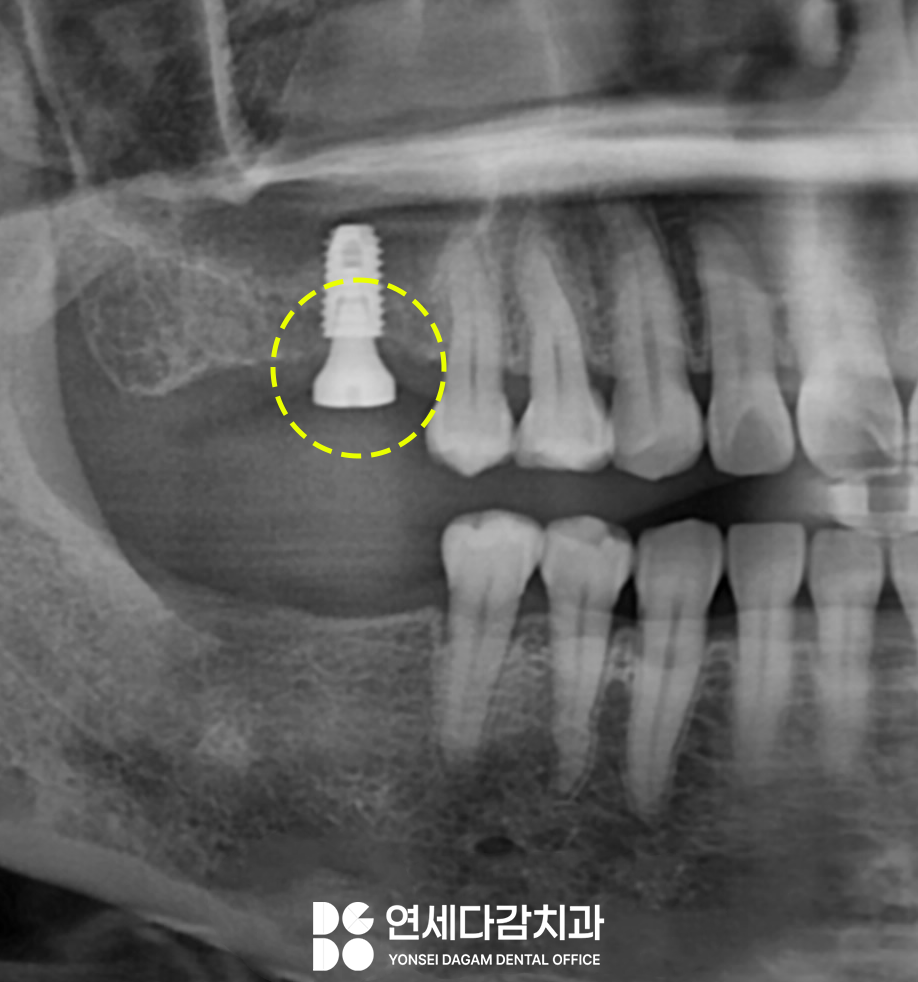

골 유착 기간을 3개월 정도를

가진 뒤 힐링 어버트먼트를

체결하였습니다.

이것은 보철을 안정적으로

장착하기 위해 그에 맞는

잇몸 형태를 만들어주는 역할을 합니다.